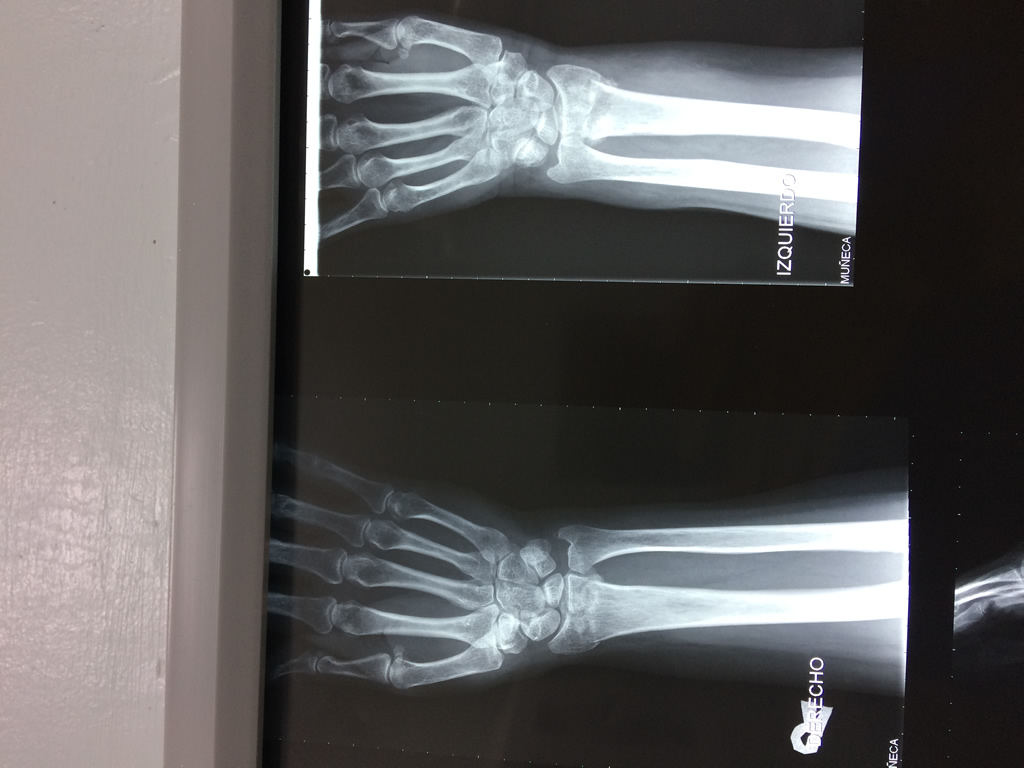

Cirugía de Muñeca y Mano

Los procedimientos más comunes en cirugía de la mano son aquellos destinados a reparar traumatismos, incluyendo lesiones de tendones, nervios, vasos sanguíneos, y articulaciones; huesos fracturados; y quemaduras, cortes, y otros daños de la piel.